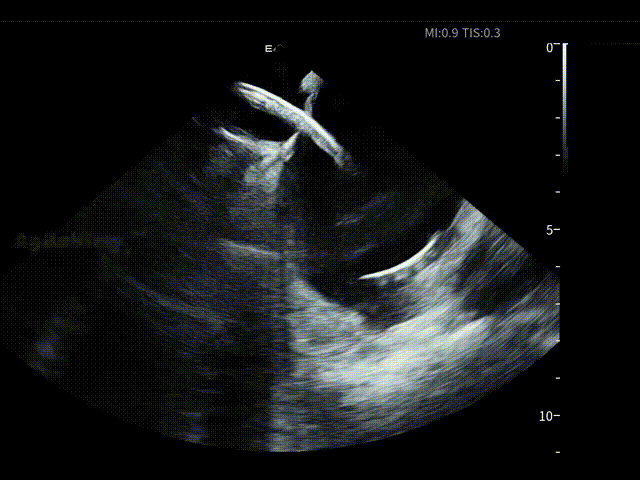

在全球最细7.5Fr ICE的持续影像引导下,手术路径清晰。随后薛枫教授在ICE下进行了房间隔穿刺,见明显tenting现象。

房间隔穿刺